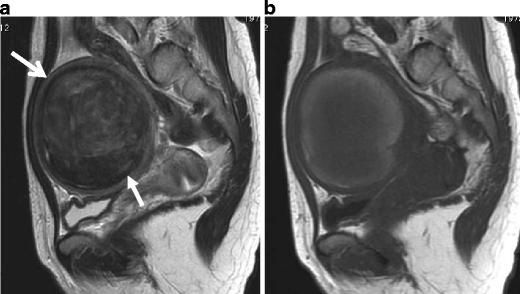

Undifferentiated stromal sarcoma in a 22-year-old female who presented with acute abdomen due to uterine rupture. a Sagittal T2-weighted image demonstrates an ill-defined myometrial mass of heterogeneous appearance in the anterior wall (arrows). The upper portion of the tumor containing fluid-fluid level represents hemorrhagic necrosis within the tumor (arrowheads). b T1-weighted image demonstrates increased signal intensity corresponding to the area of hemorrhagic necrosis (arrowheads). Hemorrhagic ascites of increased signal intensity also is present in the Douglas fossa and uterovesical fossa (asterisks). c Postcontrast T1-weighted image with fat suppression demonstrates heterogeneous enhancement within the solid component of the tumor (arrows)